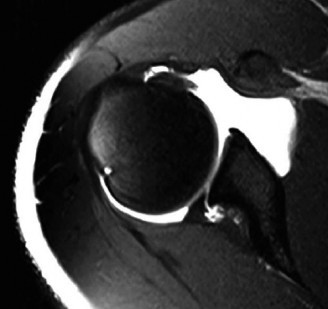

Discussion

The correct answer is (A). Medial subluxation of the biceps tendon as seen in this MRI is commonly associated with a tear of the subscapularis tendon which attaches to the lesser tuberosity. This patient’s pain may in part be attributable to the subscapular tear and this should be evaluated for during physical examination. Supraspinatus tears (Answer B) cannot be easily visualized on axial views and are not associated with medial biceps subluxations. A labral tear and ALPSA lesion (Answers C and D) are not seen on the images provided. The question stem and MRI are not suggestive of shoulder instability (Answer E). Objectives: Did you learn...? Diagnose and treat acute rotator cuff tears?

The answer is (B). As the four layers of the lateral rotator interval insert onto the lesser tuberosity of the humerus, they form the “reflection pulley” that forms a sling around the tendon of the long head of the biceps before it enters the bicipital (intertubercular) groove. A tear of the upper part of the subscapularis can disrupt this reflection pulley and destabilize the biceps tendon, allowing it to sublux or even

dislocate out of its groove, usually in a medial direction. If this happens, the intertubercular groove will be empty on MRI. Often, a “pulley sign” will also be seen on MRI when this occurs. This is when contrast material extravasates extra-articularly just over the superior border of the subscapularis tendon on axial images (see Fig. 2–11).

Figure 2–11_Axial T1 MRI. Left: an empty intertubercular sulcus, positive pulley sign (straight _black arrow on left), and dislocated biceps tendon (curved black arrow). Right: fraying subscapularis tendon (arrow). (From Lyons RP, Green A. Subscapularis tendon tears. J Am Acad Orthop Surg. 2005;13(5):353–363.)